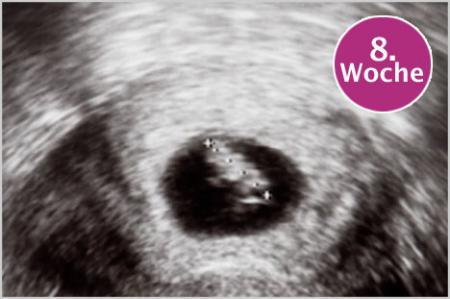

Ich häng noch mal ein Foto ran von einem Ultraschallbild in der 8ten Woche